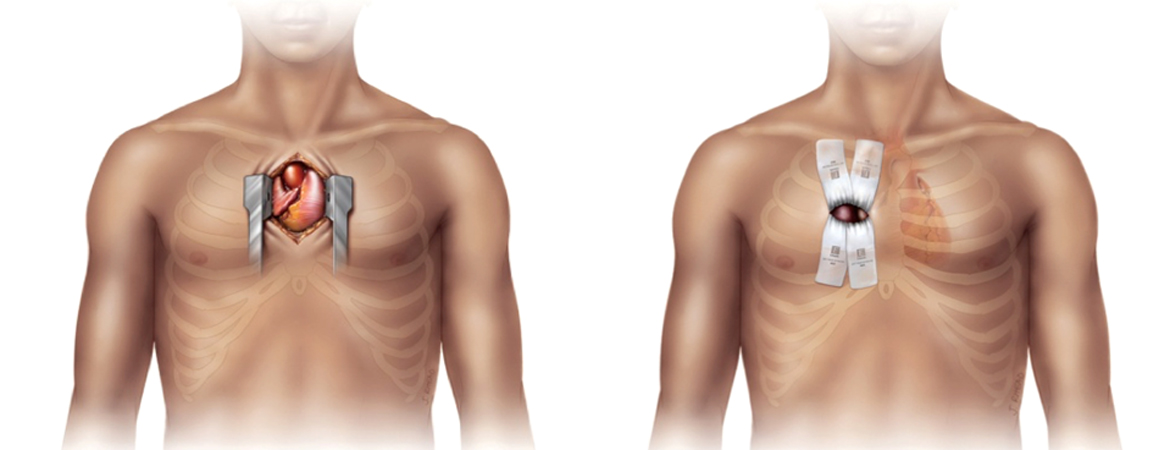

1. Design of the Swiss Atrial Fibrillation Cohort Study (Swiss-AF): structural brain damage and cognitive decline among patients with atrial fibrillation